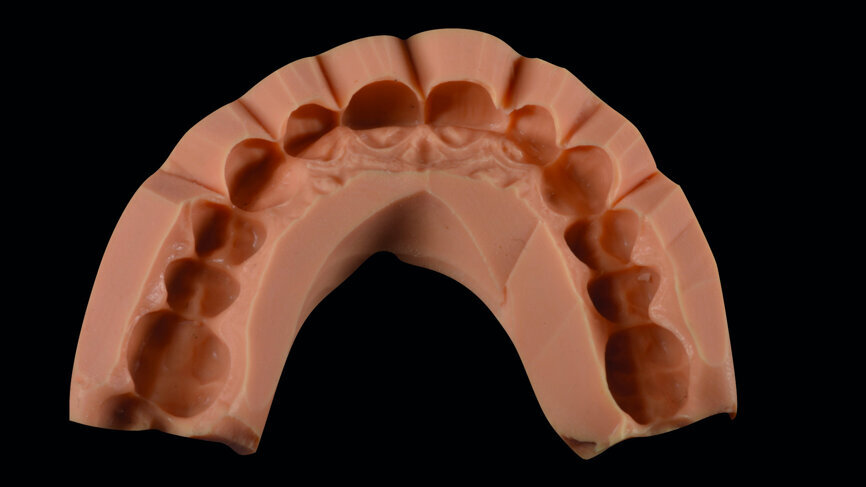

Fig. 4: Wax-up on the stone model concerning the restorative treatment of the ten anterior teeth.

Digital smile design according to Coachman and Calamita9 was performed, from which a treatment plan of crown lengthening and veneers on teeth #15–25 (Fig. 3) was proposed. A conventional diagnostic wax-up was also produced (Fig. 4). Both digital and conventional mockups were applied, and agreement was attained concerning tooth shapes and proportions. Crown lengthening was performed, guided by the digital mock-up, with the use of an acrylic transparent double crown lengthening guide that indicated the borders of the gingivectomy and alveolectomy needed in periodontal surgery for aesthetic rehabilitation (Figs. 5 & 6). [10]